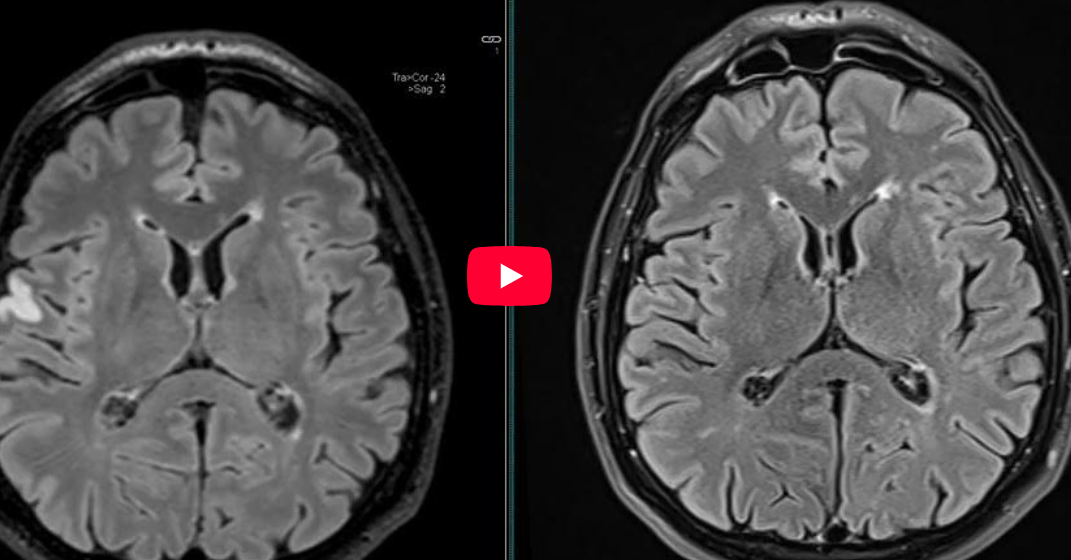

CAZ nr 87: AVC supraacut

Video 3: axial FLAIR comparativ supraacut în dreapta și trei zile mai tarziu în stânga

Discuţie caz nr 87: imaginile la prezentarea pacientului sunt realizate la 2 ore după debutul simptomelor și se poate observa restricția de difuzie a apei cu ADC redus dar fără modificarea semnalului pe secvențele FLAIR și T1; repetarea investigației după 3 zile evidențiază mărirea ariei de restricție de difuzie a apei – ce era, probabil, arie de penumbră – și apariția de modificări de semnal pe imaginile în ponderate T1 și FLAIR.

DE LUAT ACASĂ!!! Imagistica hiperacută prin rezonanță magnetică, în special secvenţa de difuzie (DWI), este foarte sensibilă pentru detectarea infarctelor cerebrale acute, chiar și foarte timpuriu după debutul accidentului vascular cerebral. IRM oferă avantaje față de CT în diagnosticul de AVC hiperacut, inclusiv capacitatea de a detecta leziuni ischemice subclinice și modificări ischemice cronice, precum și trombus intravascular. IRM multimodal, inclusiv cu secvențe de difuzie și angioRM poate fi utilizat pentru a caracteriza în continuare accidentul vascular cerebral și pentru a ajuta la selectarea pacienților pentru terapia de reperfuzie acută.